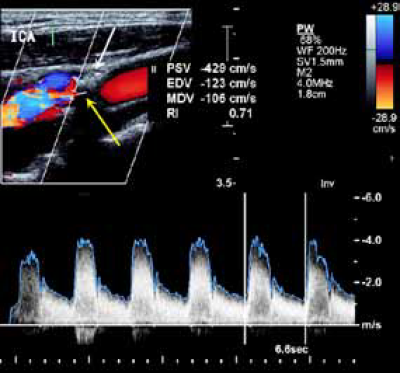

Neinvazivni dijagnostički minimum postoperativno podrazumeva neurološki, angiološki pregled i kontrolnu Duplex-sonografiju u 6-mesečnim intervalima. Većina novih lezija je ultrasonografski homogena, što ukazuje na fibroznu prirodu leziju i benignu prognozu. Identifikovanje heterogenog kompleksnog plaka je dodatni kriterijum za profilaktičnu reoperaciju. Dobar follow-up sa redovnim Duplex-sonografskim pregledima bi trebalo da detektuje restenozu pre nastanka okluzija. Hemodinamski značajna karotidna restenoza Duplex ultrasonografijom prema ESCT16 kriterijumima ima PSV (peak sistolic velocity) > 230cm/sec. U tom slučaju indikovana je provera multislajsnom kompjuterizovanom tomografijom (MSCT) supraaortičnih grana.

Duplex-ultrasonografski nalaz postoperativno: Turbulencija na mestu male neravnine na distalnom kraju endarterektomije,

In stent restenoza unutrašnje karotidne arterije nakon

PTA.

Spektralna analiza, uredan nalaz po implantaciji stenta zbog resstenoze